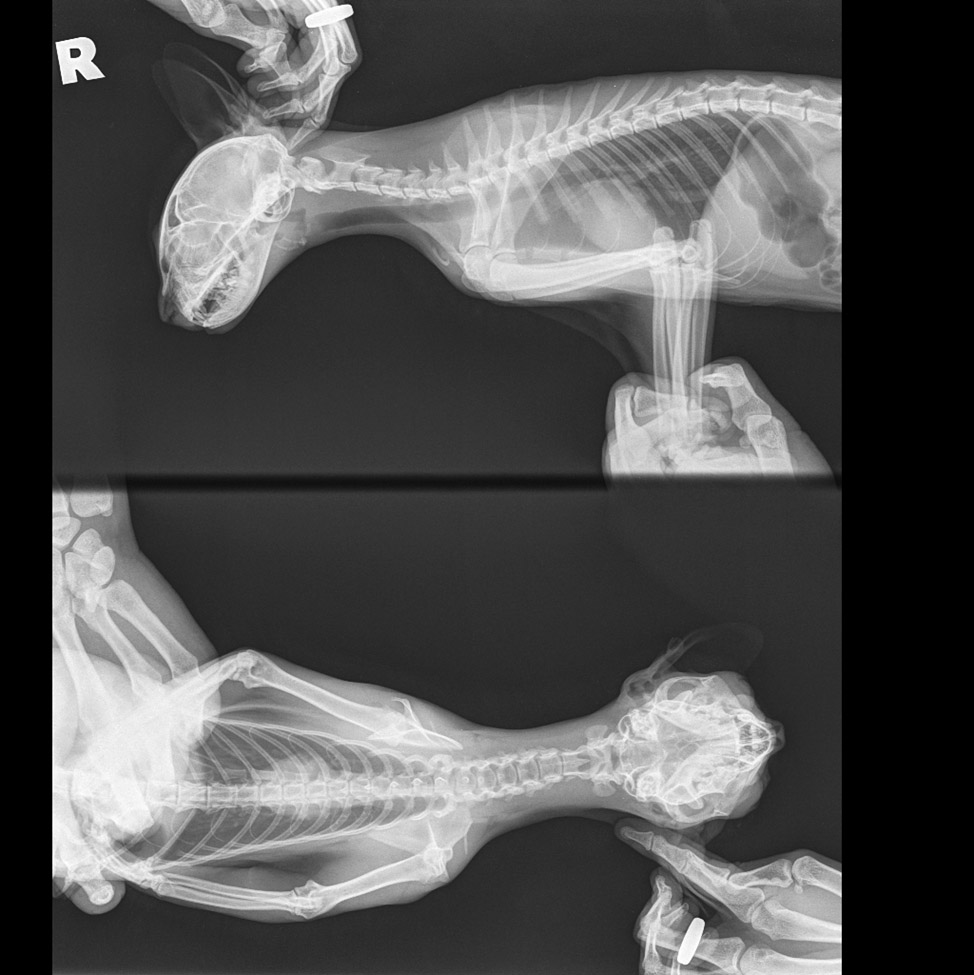

Рентгеновские снимки головы кошки в боковой проекции